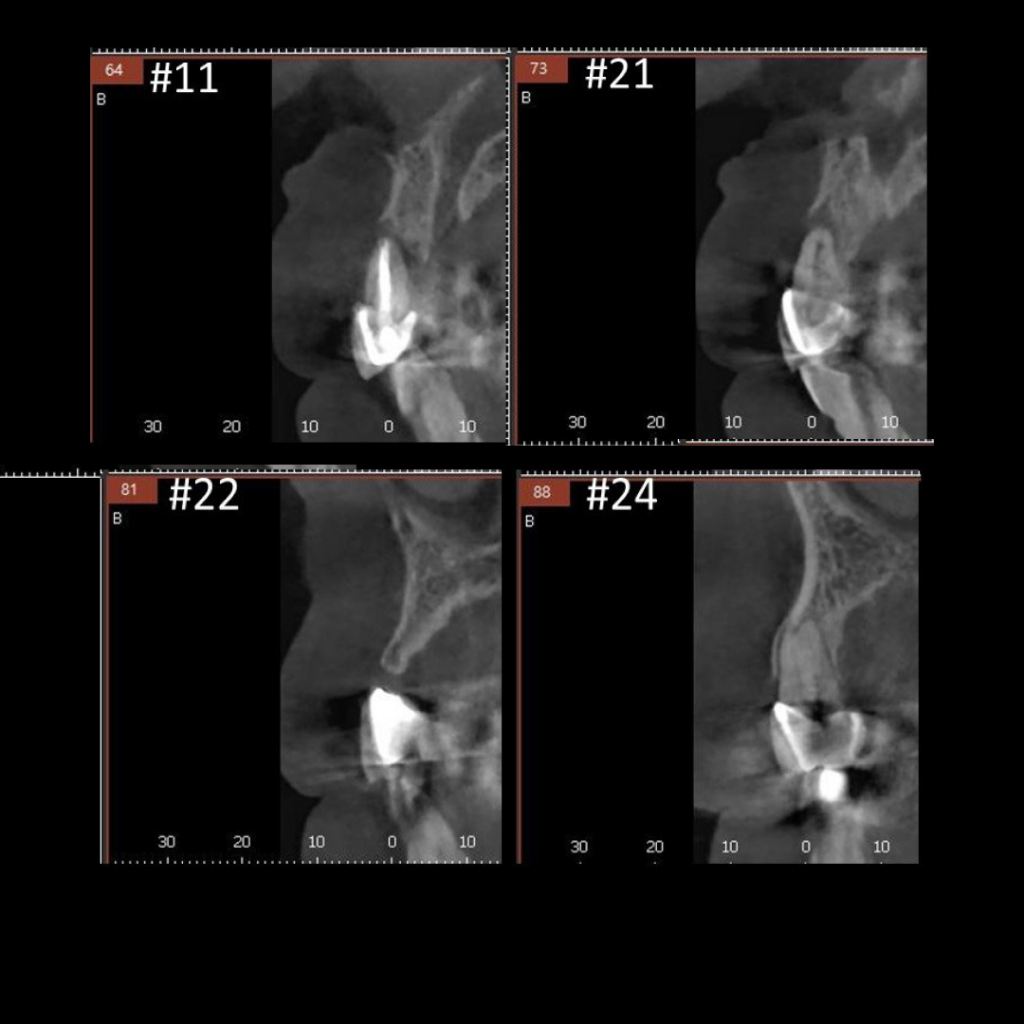

- Удаление несъемного мостовидного протеза по причине подвижности во фронтальной области верхней челюсти с диагнозом "Хронический генерализованный парадонтит и множественный кариес"

- Проведение имплантации AnyRidge с немедленной нагрузкой

- Заполнение костных дефектов смесью из костного материала TI-oss, аутокости пациента и обогащенной тромбоцитами плазмой PRP